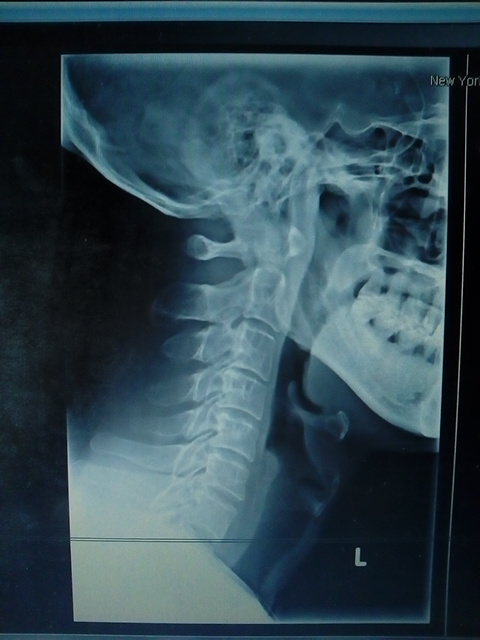

I have been asking for the two sets of X-Ray studies done at New York

Medical & Diagnostic Center (80-46 Kew Gardens Rd, Kew Gardens, NY 11415).

They have denied my access to an X-Ray image of

open-mouth view. Today, they gave me a CD with handwritten “copy of ALL X-

RAYS”, and I brought it to some place, and Was told that it still doesn't

have the open-mouth view image. When I ran that CD’s program on the own

computer, my computer immediately crashed. The reboot screen said something

of “no MBR”.